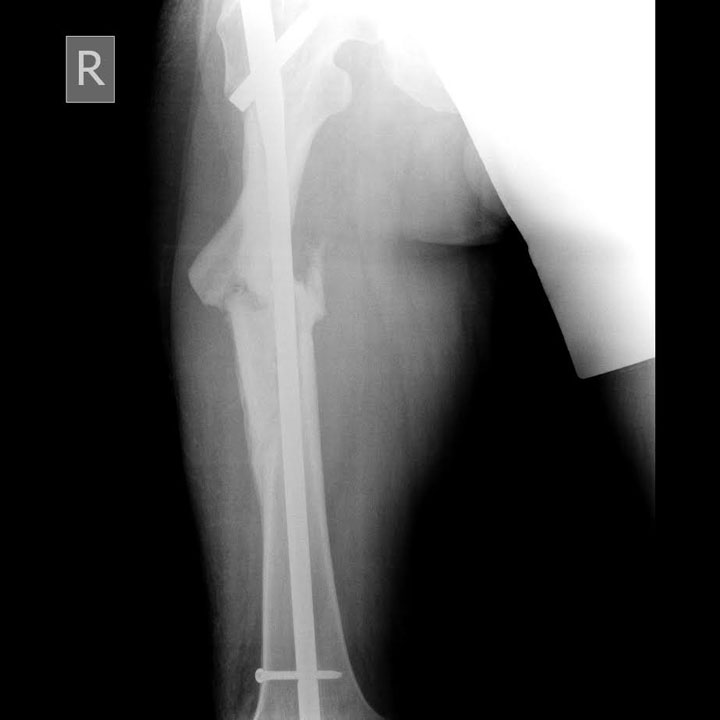

- Да, мы сделали пациенту закрытый интрамедуллярный остеосинтез. Суть его заключается в том, что в кость через небольшой (3-4 см) разрез вводится специальный штифт. Он вводится в кость вдали от места перелома, что снижает риск послеоперационных осложнений.

Преимуществами закрытого интрамедуллярного остеосинтеза являются малая травматичность хирургического вмешательства, минимальная потеря крови во время и после операции, возможность одномоментно провести остеосинтез переломов в нескольких местах. К тому же этот метод обеспечивает отличный косметический результат.

- В большинстве случаев блокированный интрамедуллярный стержень или штифт настолько прочно фиксирует поврежденную кость, что уже на следующие сутки после операции пациенту разрешаются дозированная нагрузка на травмированную руку или ногу.

Результат остеосинтеза - рентгенснимок после операции